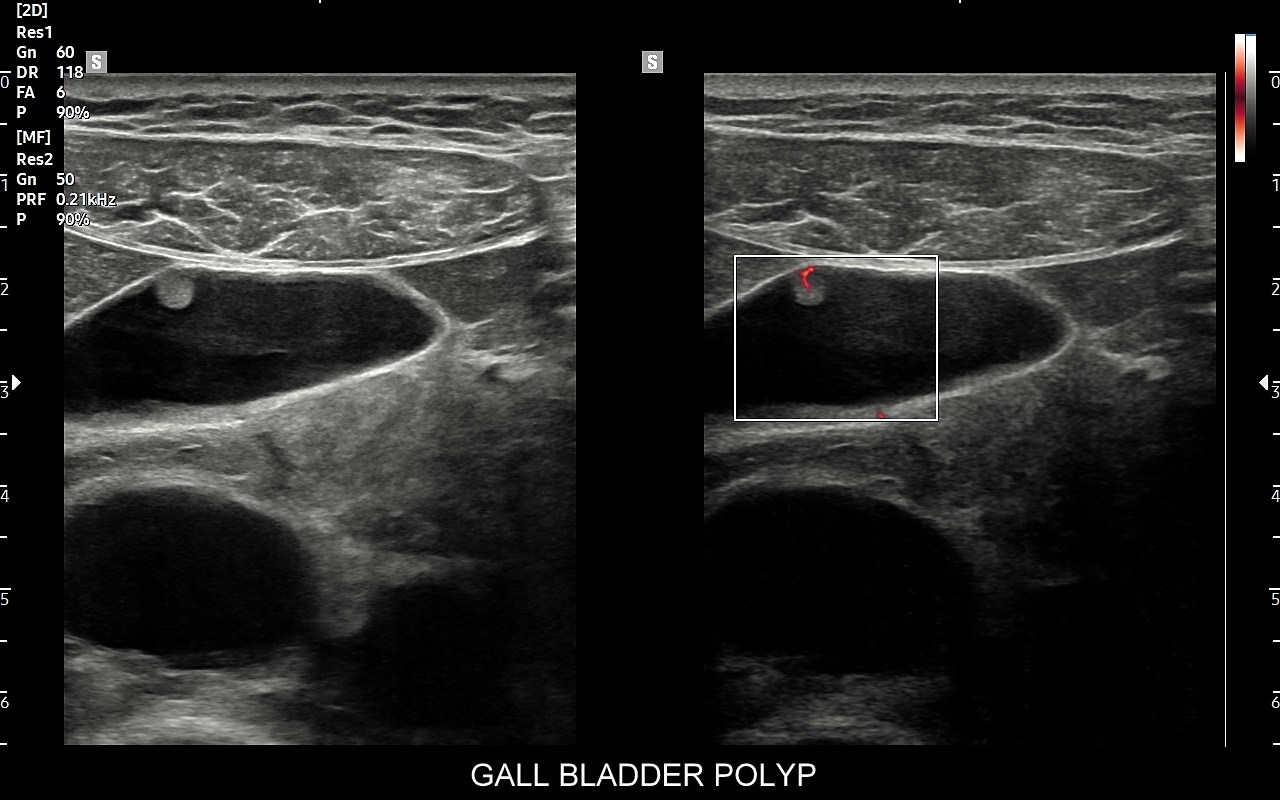

Rozwinięciem standardowego badania USG jamy brzusznej jest badanie multiparametryczne MPUS (ang. multiparametric ultrasound), w ramach którego wykorzystuje się różnorodne, nowoczesne modalności sonograficzne, takie jak tryby mikrounaczynienia MVI, B-flow, elastografię, ilościową ocenę stłuszczenia wątroby QUS, czy tryb Dopplera spektralnego, a to wszystko w celu uzyskania dodatkowej oceny funkcjonalnej i biologicznej struktur, narządów oraz tkanek jamy brzusznej. Obrazowanie MPUS niejednokrotnie poprawia także wizualną ocenę narządów wewnętrznych, czego przykładem jest zastosowanie trybu MVI w ramach bezkontrastowej angiografii sonograficznej naczyń oraz w ocenie guzów nerek. Klasycznymi i najczęstszymi zastosowaniami badania MPUS są jednakże funkcjonalna ocena wątroby w kierunku stłuszczenia, zwłóknienia, zapalenia i nadciśnienia wrotnego, a także ocena żywotności i funkcji nerek.

• Możliwość rozszerzenia zakresu badania USG w razie wystąpienia konieczności. Praktycznymi przykładami są zastosowanie trybu MVI w przypadku wykrycia guzka w nerce, czy przeprowadzenie badania elastograficznego i dopplerowskiego w wypadku stwierdzenia nieprawidłowego obrazu wątroby.